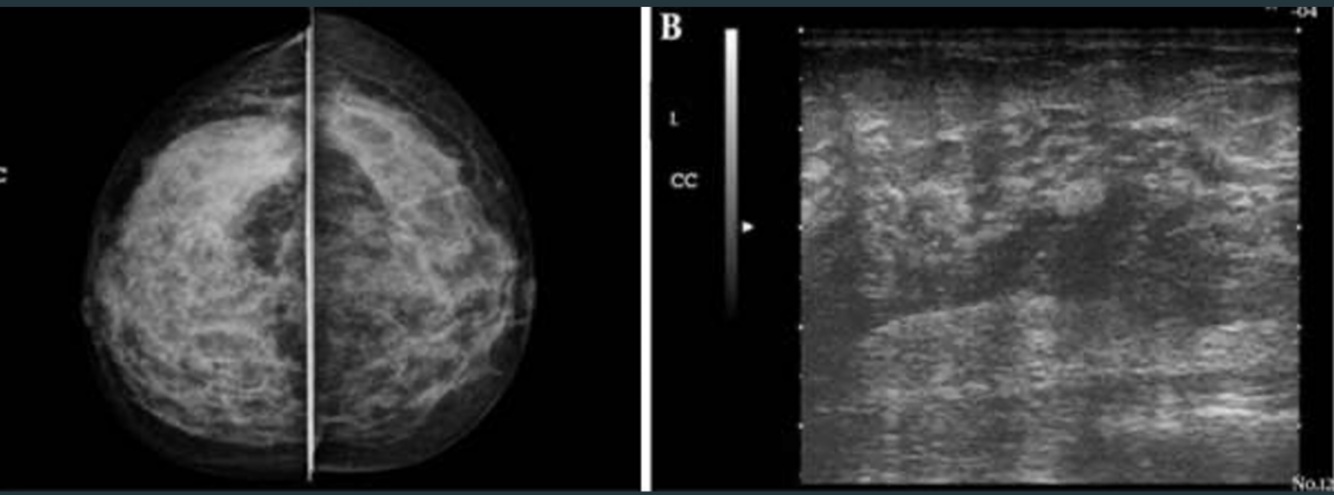

Dx

A

Mastitis

Q